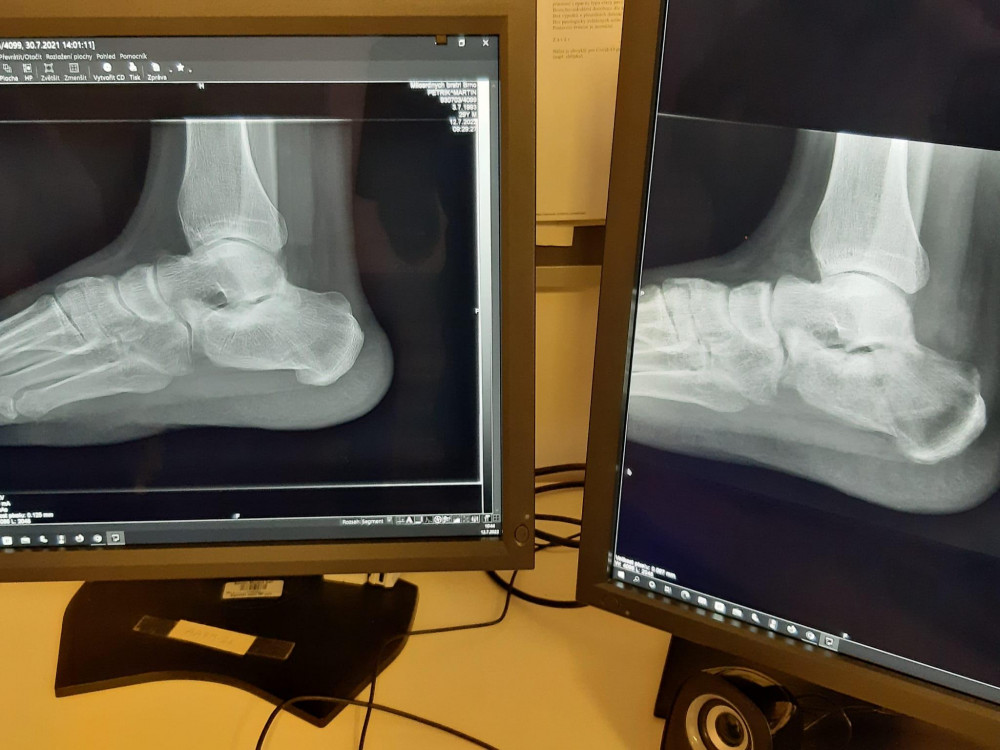

Rentgen_ rozdil vykresleni snimku